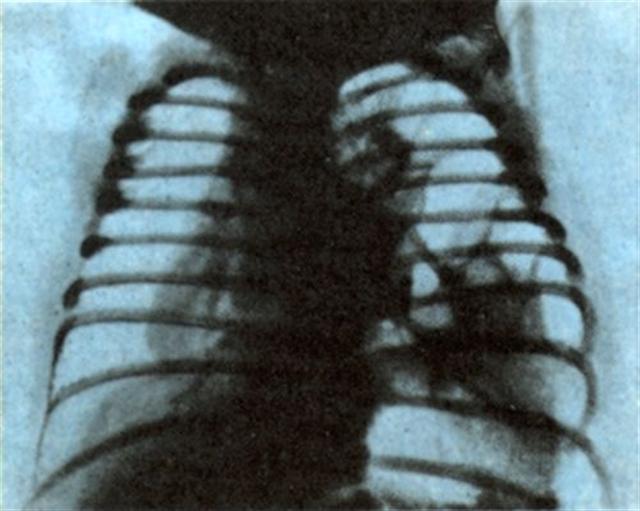

Рис. 2. Рентгенограмма грудной клетки ребенка с врожденной левосторонней диафрагмальной грыжей (прямая проекция): субтотальное затемнение левого легочного поля, обусловленное диафрагмальной грыжей.